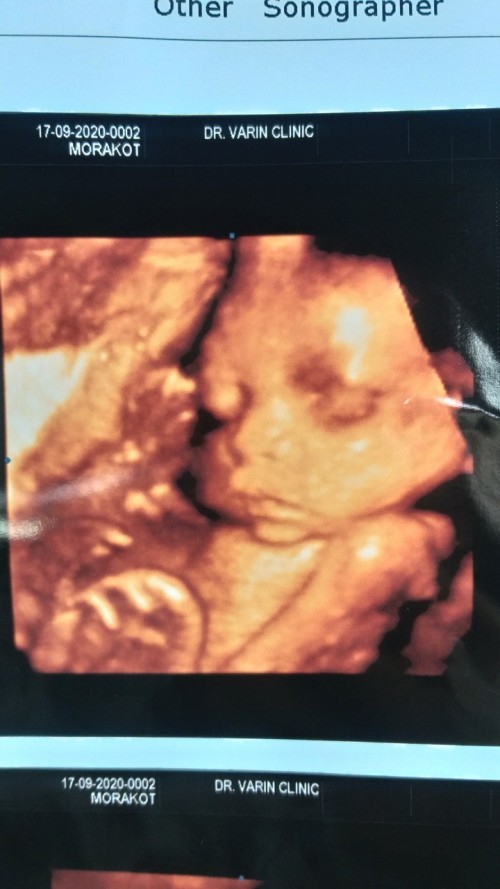

มาอวดรูปตอนซาวด์กันหน่อยค่ะ แม่ๆกำหนดคลอดเดือนไหนบ้างคะ